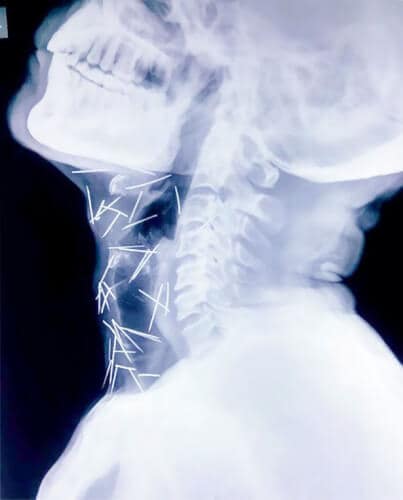

En prenant d’autres radiographies du corps de Badrilal Meena, les médecins ont fait une étrange découverte. Au total, 75 aiguilles (dont 40 dans sa gorge) lui ont été extraites.

Depuis quelques mois, Badrilal Meena se plaignait de vives douleurs à l’orteil. Les médecins ont logiquement choisi de l’opérer à Kota (Rajasthan, Inde). C’est alors qu’ils ont découvert vingt épingles et aiguilles au niveau de la jambe droite de cet homme de 56 ans.

Mais ce n’est pas tout. En prenant d’autres radiographies de son corps, les médecins ont fait une étrange découverte. Au total, 75 aiguilles (dont 40 dans sa gorge) lui ont été extraites.

Ni le patient ni sa famille ne savent comment ces objets se sont introduits dans son corps. Les médecins restent convaincus qu’ils ont été avalés de façon délibérée.

“Nous étions si inquiets quand nous avons vu les images”, a déclaré Rajendra, le fils du patient, dans le Mirror.” Nous ne savons pas comment les aiguilles ont fini dans son corps. Je lui ai posé la question à maintes reprises mais il ne se souvient de rien.”

Badrilal Meena s’en sort plutôt bien puisque ses organes n’ont pas été touchés.